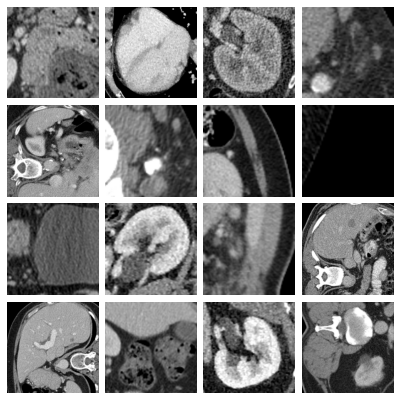

- organs_axial, Axial Organ Slices:

-

Dataset of axial image slices of 11 different organs, extracted from the Liver Tumor Segmentation Benchmark (LiTS) dataset [bilic2023liver] and the corresponding organ bounding box annotations from [xu2019efficient]. We derived a multi-class organ classification task with 11 labels by extracting a cropped image of each individual organ in each of the CT volumes using the bounding box annotations. We obtained a total of 1,645 organ images images. We removed 106 images for which the voxel size information was missing. The axes on one image were permuted to bring it to the same format as the other images. The images and masks were sliced from the original 3D volumes by taking the center of the organ bounding box in the axial plane. The Hounsfield-Units of the images were transformed into grayscale images by applying a window with a width of 400 and a level of 50, which are typical values for abdominal CT imaging. The images and masks were cropped to a square size in the physical space, by centering at the center of the bounding box and expanding the smaller side. The resulting images and masks were resized to pixels using bi-cubic and nearest neighbor interpolation, respectively. For visualization purposes, we additionally provide images averaged over the 10% central slices with the projected bounding boxes of all organs extracted from the image drawn on top.

- organs_coronal, Coronal Organ Slices:

Dataset of coronal image slices of 11 different organs, extracted from the LiTS dataset. The images were processed the same as described for the Axial Organ Slices dataset, except that the coronal projections were used.

- organs_sagittal, Sagittal Organ Slices:

Dataset of sagittal image slices of 11 different organs, extracted from the LiTS dataset. The images were processed the same as described for the Axial Organ Slices dataset, except that the sagittal projections were used.